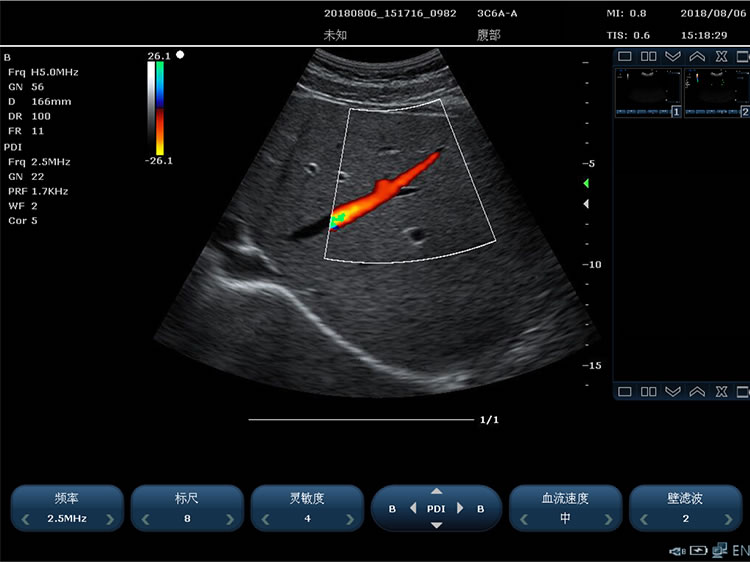

3)Power Doppler imaging

1)Imaging modes including: B Mode, 2B Mode, 4B Mode, M Mode, Color(Color Doppler) Mode, PDI(Power Doppler) Mode, PW Mode, CW Mode, Dissection M, B+C+PW three modes, B+PDI+PW three modes, support single window display, double window real-time display, four windows display

Color Doppler technique requirements:

1)The doppler gain is continuously adjustable

2)Color enhancement